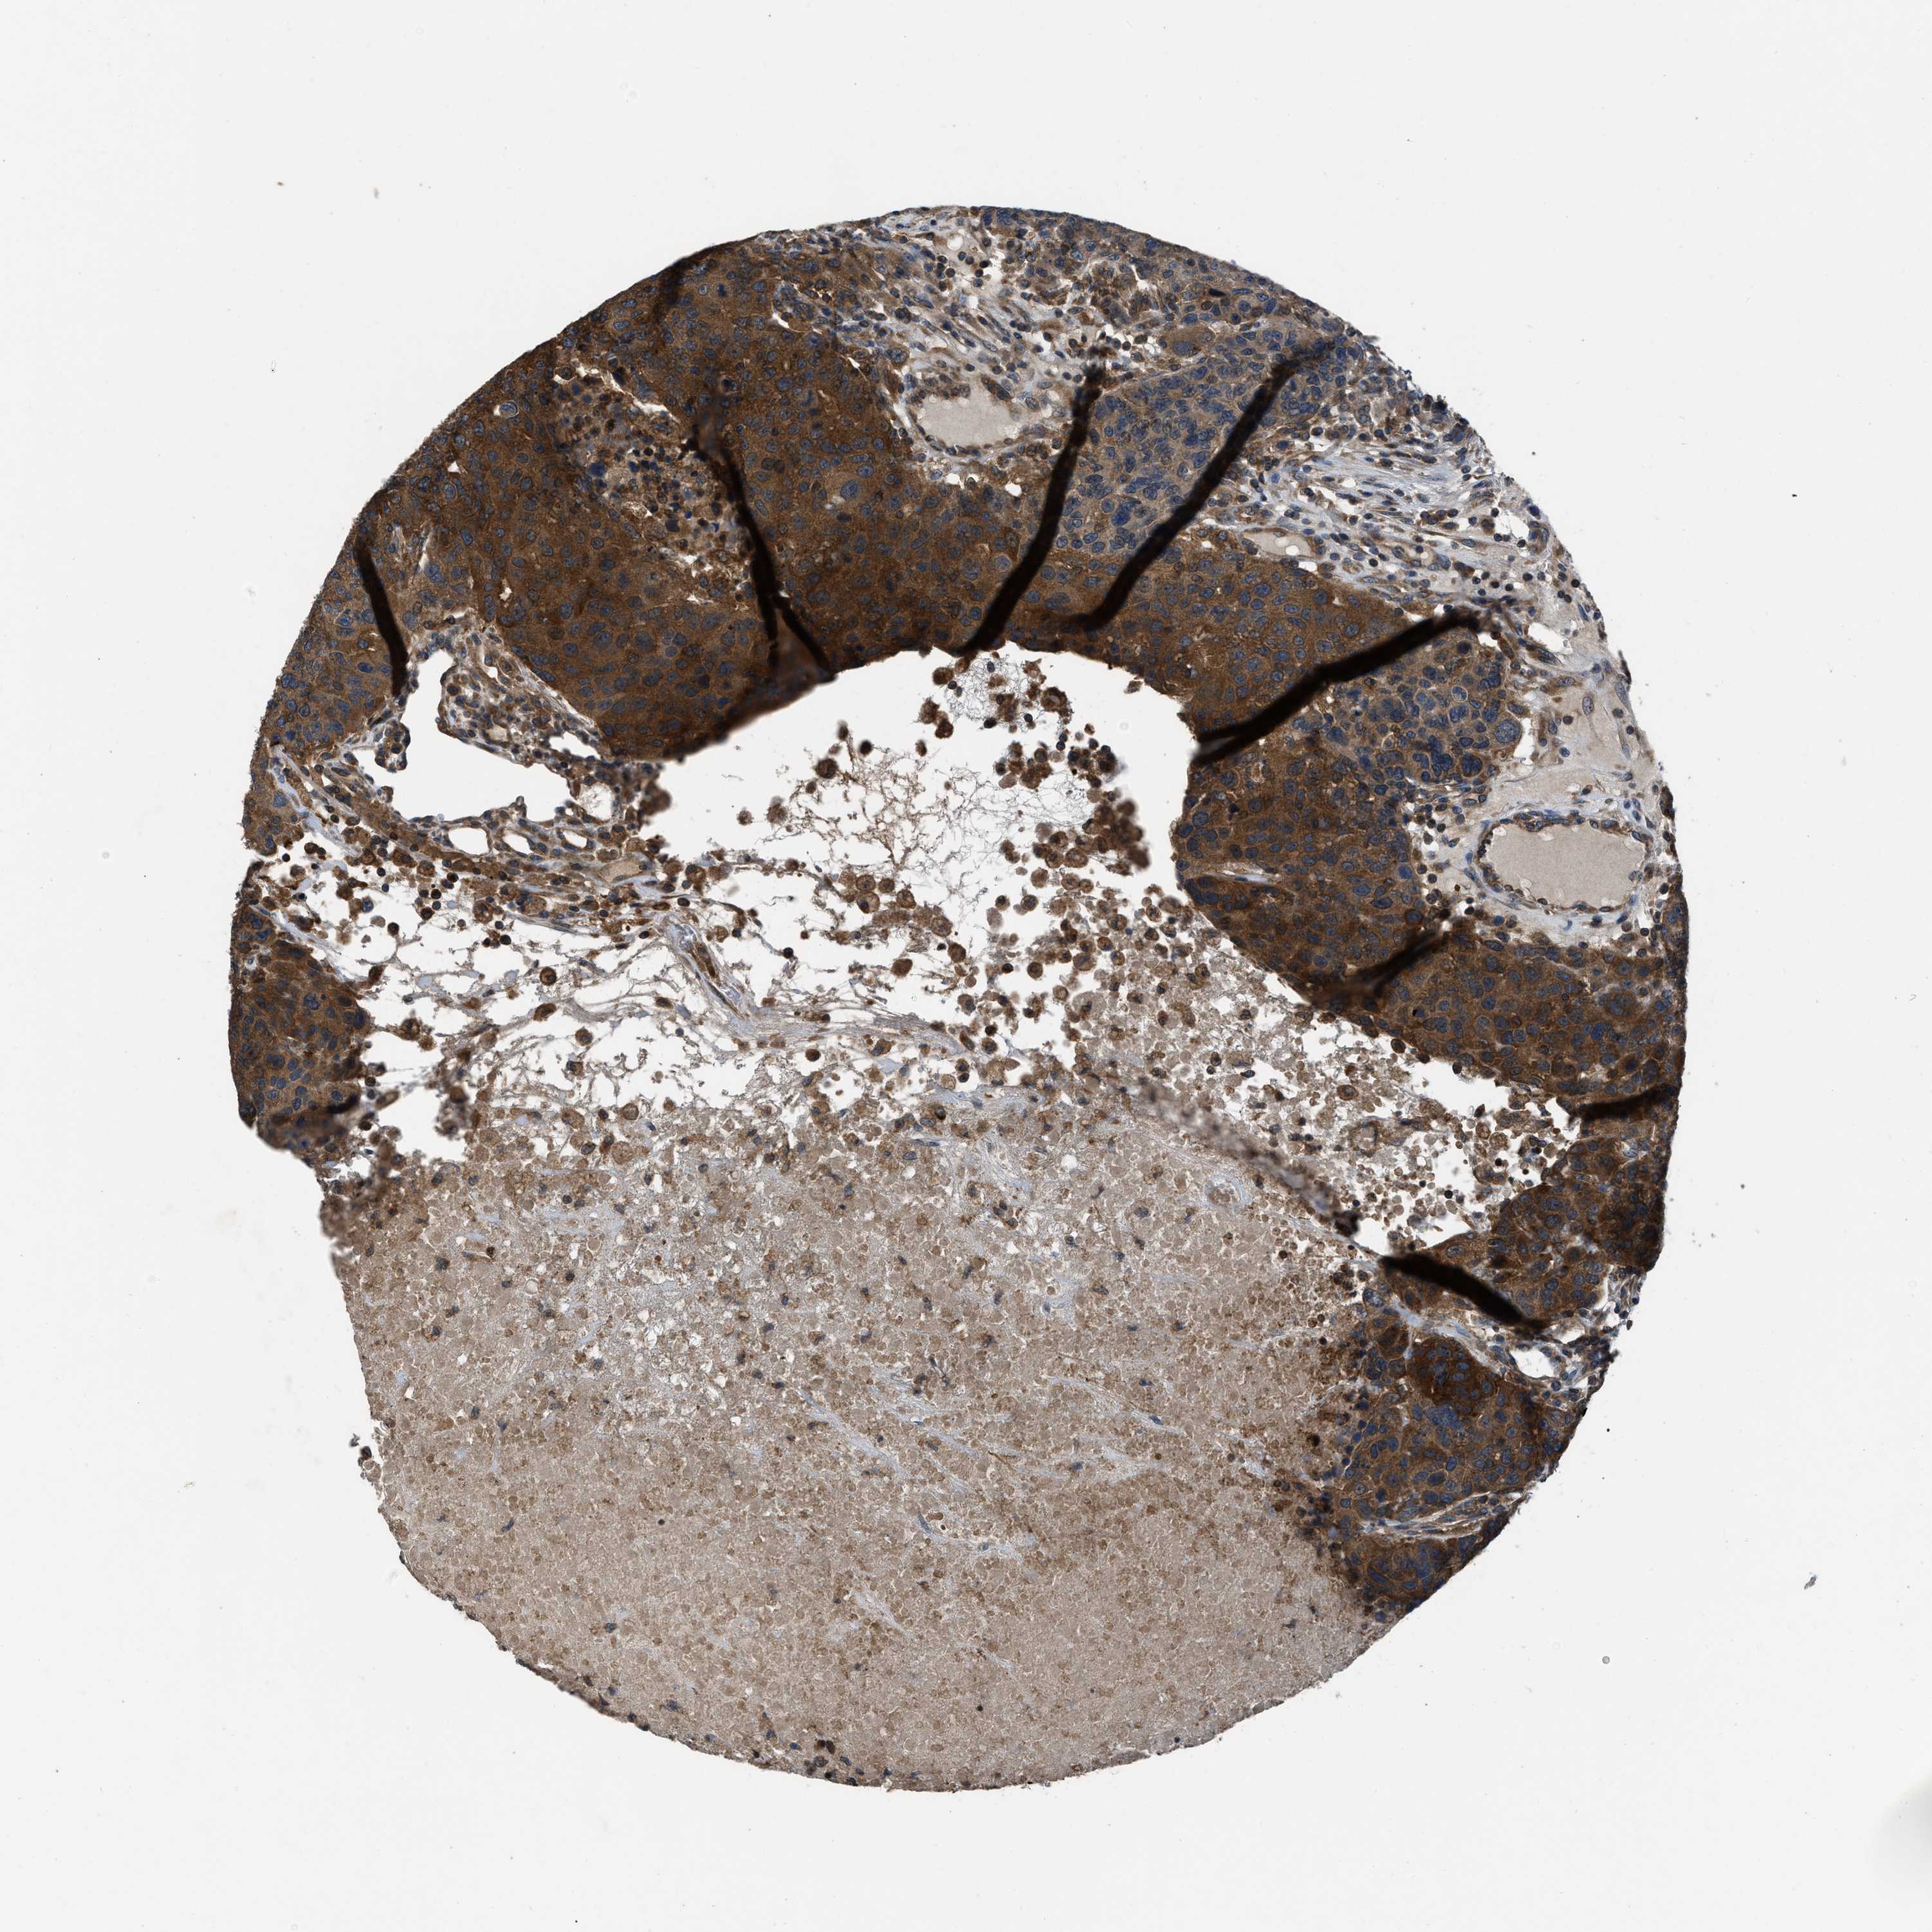

CANCER BREAST CANCER Show tissue menu

BRCA TCGA BRCA VALIDATION PROTEIN EXPRESSION